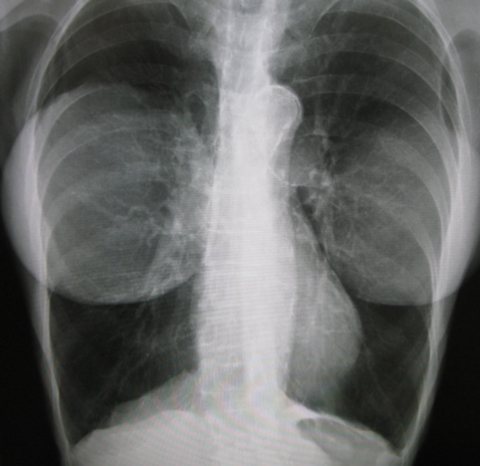

가슴수술 엑스레이